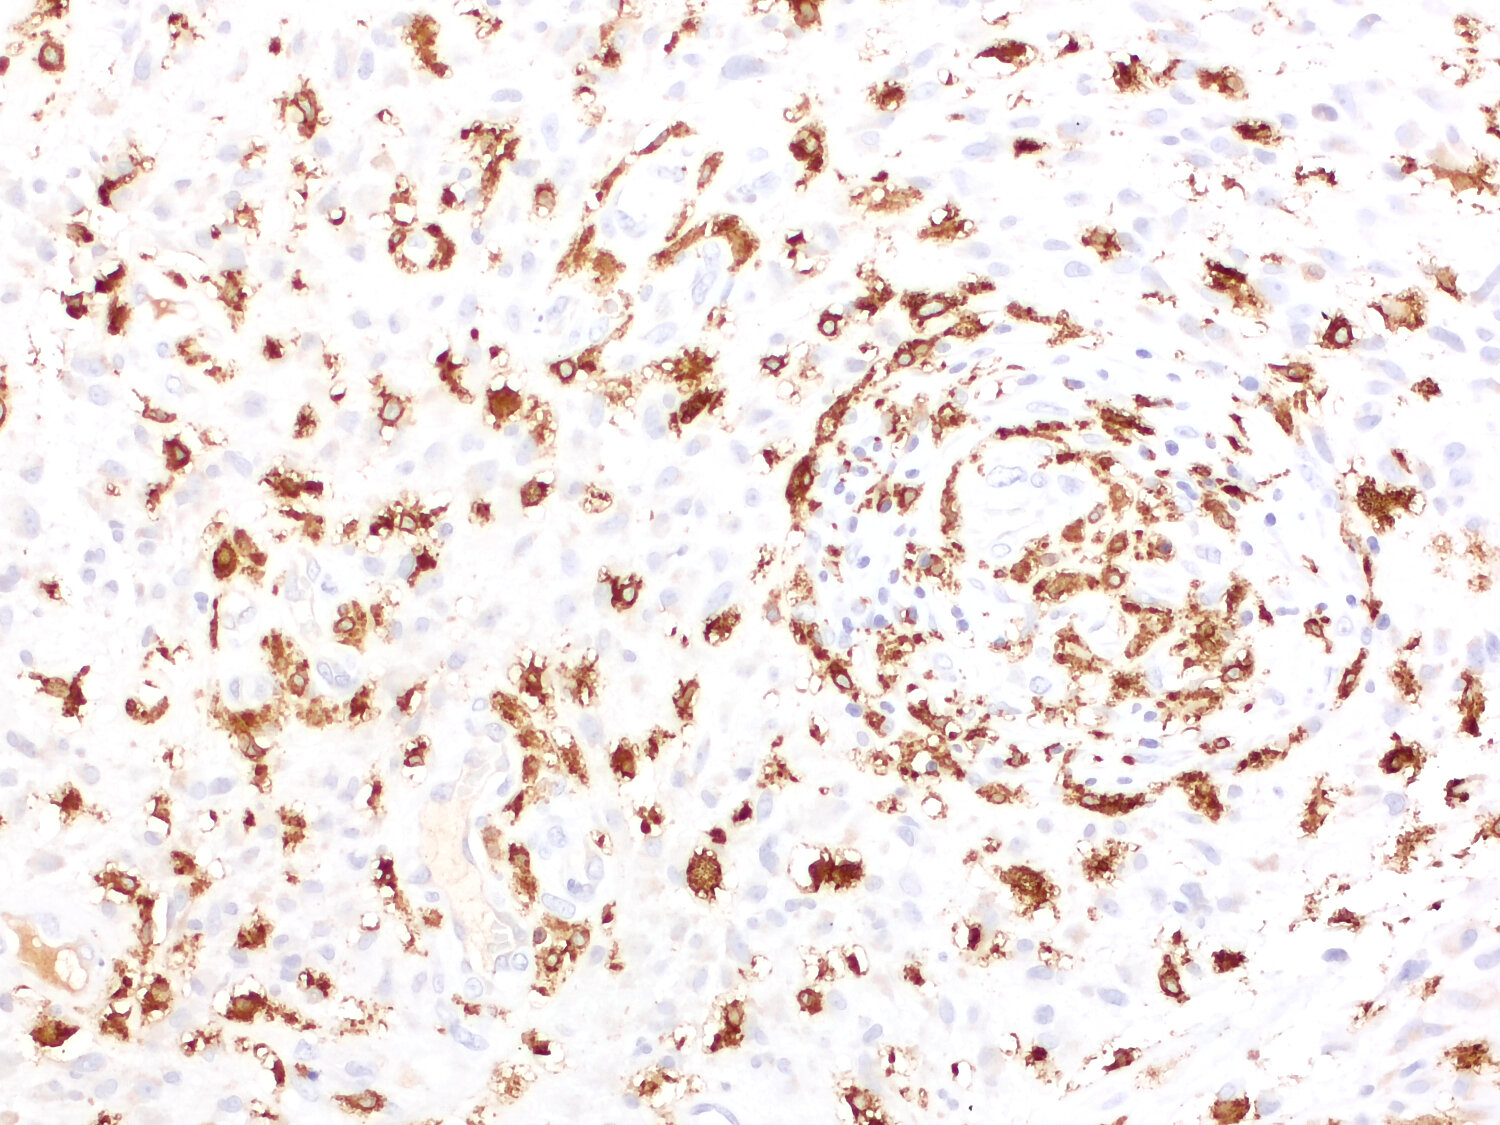

Rabbit anti-human CD163 stains only CD163-positive cells in human liver. It does no stain CD163 in murine CD163-positive cells in mouse liver.